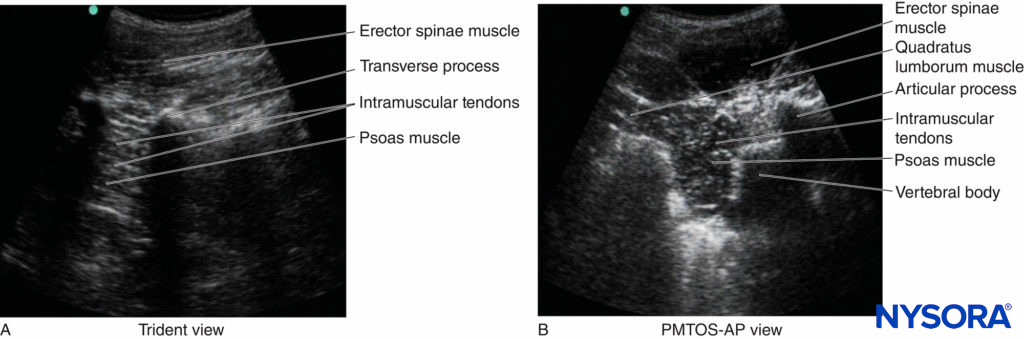

On a sagittal sonogram, the lumbar transverse processes are identified by their hyperechoic reflection and an anterior acoustic shadow (see Figures 11 and 12), which is typical of bone. The acoustic shadow of the transverse processes produces a sonographic pattern referred to as the “trident sign” (see Figures 11 and 12) because of its similarity in shape to a trident (in Latin, tridens or tridentis).

The psoas muscle is visualized through the acoustic window (see Figures 11 and 12) of the trident as multiple longitudinal hyperechoic striations against a hypoechoic background typical of muscle (see Figure 11). The lumbar plexus nerves are seen as longitudinal hyperechoic structures in the posterior aspect of the psoas muscle (see Figure 11) One should note that not all hyperechoic shadows or striations within the psoas muscle are nerves because the psoas muscle contains intramuscular tendons, which also produce hyperechoic shadows (Figure 20).

On a typical PMTOS-TP (see Figure 10b), the erector spinae muscle, transverse process, psoas major muscle, quadratus lumborum muscle, and anterolateral surface of the vertebral body are clearly visualized (see Figure 13).

The psoas muscle appears hypoechoic, but multiple areas of hyperechogenicity are also interspersed within the central part of the muscle (see Figure 13). These hyperechoic speckles represent the intramuscular tendon fibers of the psoas muscle and are more pronounced below the level of the iliac crest.

1. USG LPB Using the Trident View

As described above, a paramedian sagittal scan is performed with the patient in the lateral decubitus position, with the side to be blocked uppermost (see Figure 9 and 10). Once an optimal view of the lumbar US trident is obtained (Figure 22), an insulated nerve block needle, connected to a nerve stimulator, is inserted in plane from the caudal end of the US transducer (see Figure 22).

FIGURE 22. Sagittal sonogram of the lumbar paravertebral region showing the “trident” view. The psoas muscle is seen in the acoustic window between the transverse processes and is recognized by its typical striated appearance. Part of the lumbar plexus is also seen as a hyperechoic shadow in the posterior aspect of the psoas muscle between the transverse processes of the L3 and L4 vertebrae. The inset photograph shows the orientation of the US transducer and the direction in which the block needle is introduced (in plane) during a USG LPB via the trident view.

The aim is to guide the block needle through the acoustic window of the lumbar US trident; that is, through the space between the transverse process of L3 and L4 into the posterior aspect of the psoas major muscle until either needle–nerve contact is visualized or an ipsilateral quadriceps muscle contraction is elicited. After negative aspiration, an appropriate dose of local anesthetic (20–25 mL of 0.5% ropivacaine or levobupivacaine) is injected in aliquots over 2–3 minutes and the patient is closely monitored.

Spread of local anesthetic within the posterior aspect of the psoas muscle can be visualized in real time, and the nerves of the lumbar plexus are better visualized after the local anesthetic injection (see Figure 22).